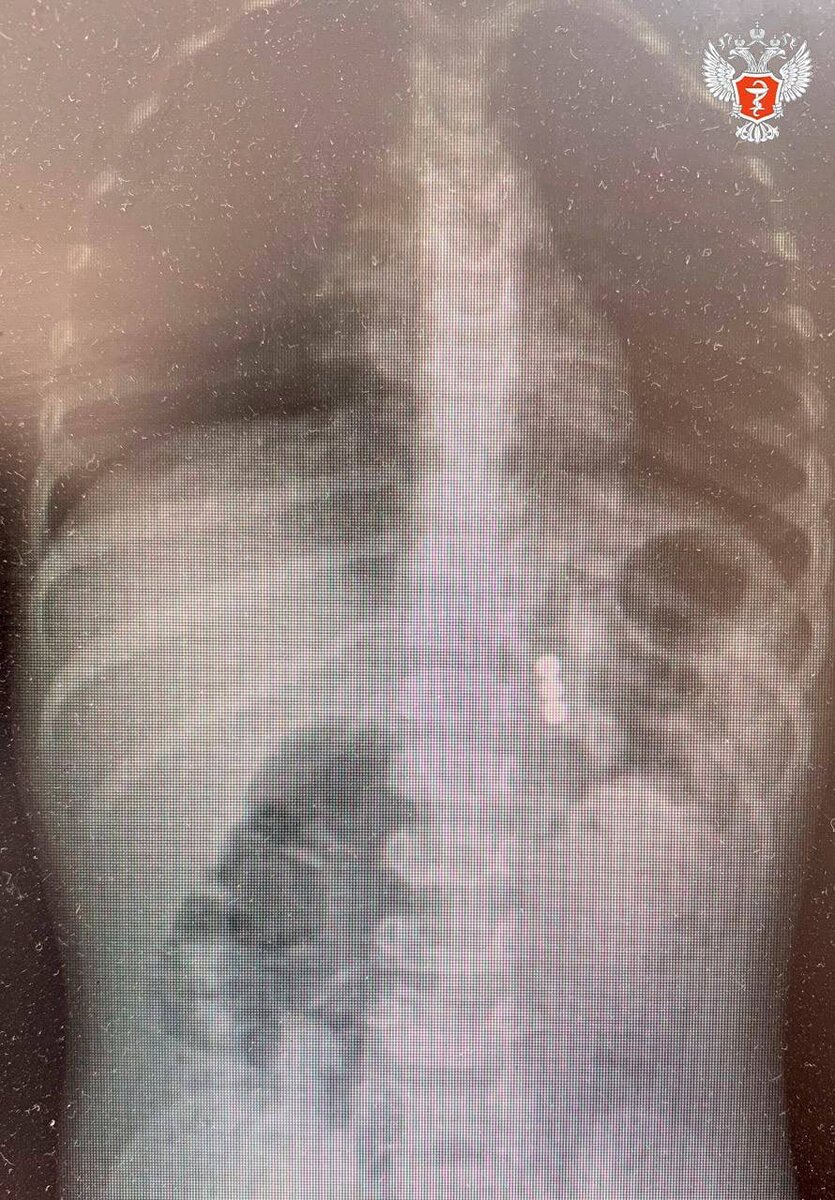

Однако контрольный рентген показал, что три магнита остались в организме и находились уже за пределами досягаемости эндоскопа.

Специалисты Областной детской клинической больницы №2 в Воронеже провели сложную операцию по спасению двухлетнего ребенка, проглотившего множество магнитов. Маленький пациент поступил в приемное отделение больницы. Обследование выявило серьезную проблему: в желудке ребенка находилось скопление инородных предметов – конгломерат из магнитов. Об этом сообщает пресс-служба Минздрава России. Первым этапом помощи стала гастроскопия. - Мы провели гастроскопию, в ходе которой последовательно извлекли 45 магнитов и металлический шарик из желудка, – рассказал заведующий эндоскопическим отделением Александр Климов. Однако контрольный рентген показал, что три магнита остались в организме и находились уже за пределами досягаемости эндоскопа. - Выяснилось, что ребенок глотал магниты в разное время, – пояснил детский хирург Сергей Мясоедов. – поэтому некоторые из них уже успели переместиться в кишечник. Двигаясь по ЖКТ, они сцепились и притянули друг к другу стенки желудка и кишечника. Извлечь оставш